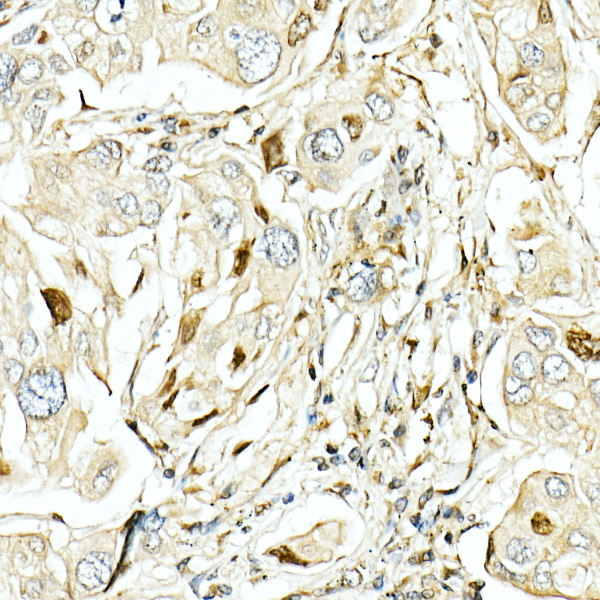

Cell autophagy is a highly conservative process in eukaryotes. Proteins from the ATG family play a key role in this process. Other proteins such as mTOR, beclin1, and FoxO also play important regulatory roles in autophagy. LC3 protein is a central indicator of cellular autophagy. LC3 undergoes posttranslational modification during autophagy. LC3 carboxy-terminal cleavage forms LC3-I (16KD) and is then lipidated to LC3-II (14KD) – the key protein in autophage formation. The concentration of LC3-II determines the standard of autophagy.